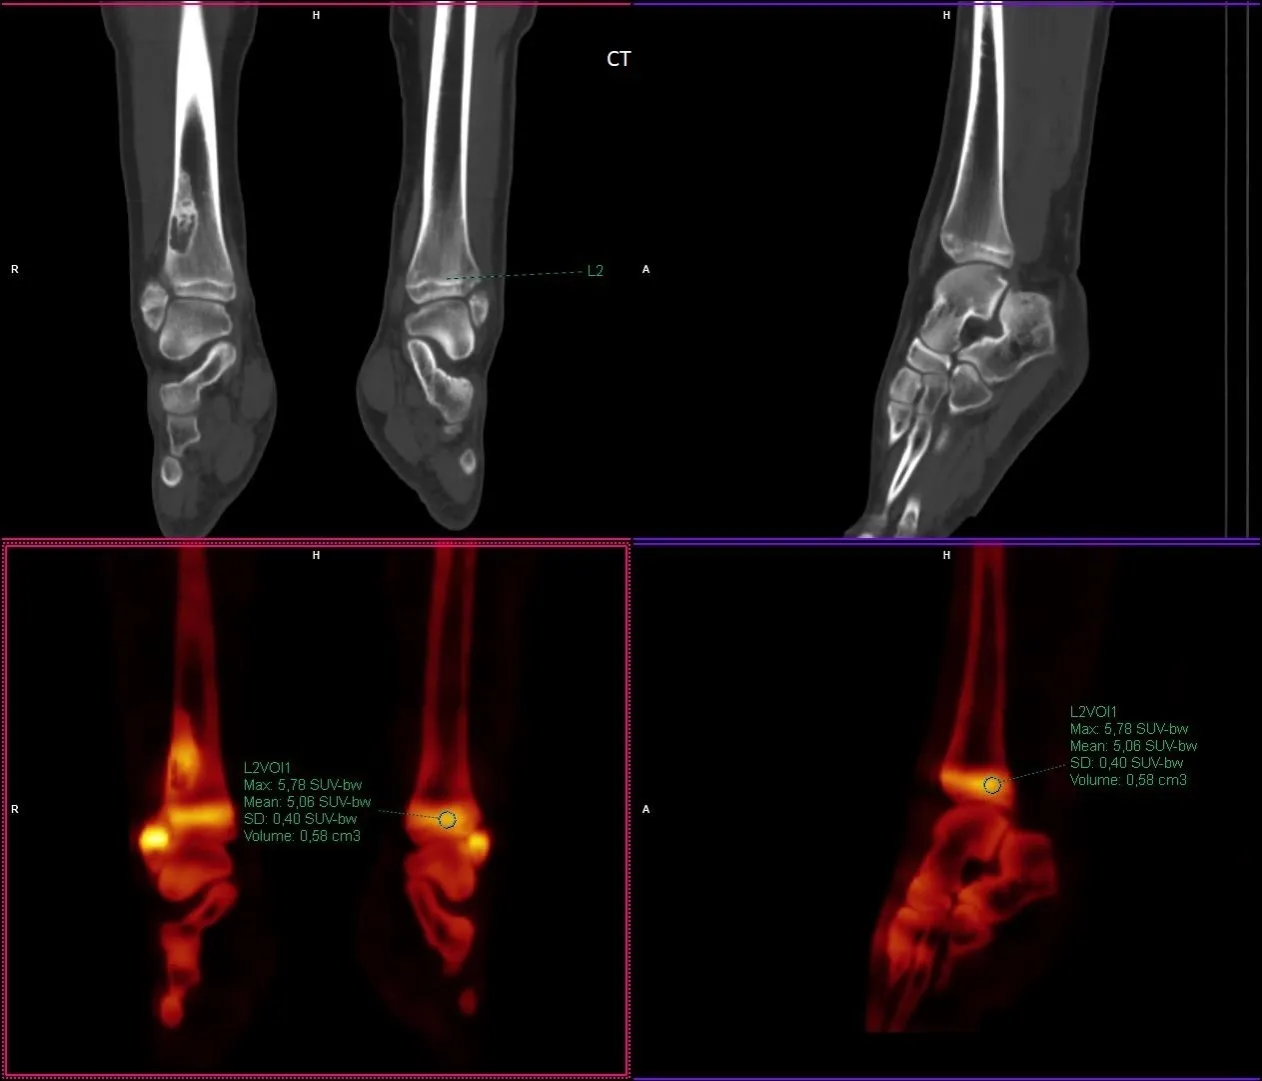

SUV max to wskaźnik, który odzwierciedla maksymalną wartość zliczeń dla pojedynczego voksela w danym obszarze zainteresowania, uzyskiwaną podczas badań obrazowych, takich jak PET/CT lub SPECT/CT. Wartość ta informuje lekarzy o najwyższej intensywności wychwytu radiofarmaceutyku w badanej tkance, co ma kluczowe znaczenie w diagnostyce chorób, w tym nowotworów. Dzięki SUV max możliwe jest lepsze zrozumienie metabolicznej aktywności tkanek, co pozwala na bardziej precyzyjne podejmowanie decyzji klinicznych.

W badaniach obrazowych, takich jak PET/CT i SPECT/CT, SUV max jest niezwykle ważnym wskaźnikiem, który pozwala na ocenę stanu zdrowia pacjentów. Dzięki niemu lekarze mogą zidentyfikować obszary o podwyższonej aktywności metabolicznej, co może wskazywać na obecność nowotworów, stanów zapalnych czy innych chorób. Wartości SUV max są wykorzystywane do oceny skuteczności leczenia oraz do planowania dalszej diagnostyki.